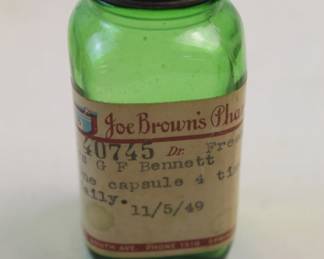

1117 - Vintage Medicine Bottles and Jars